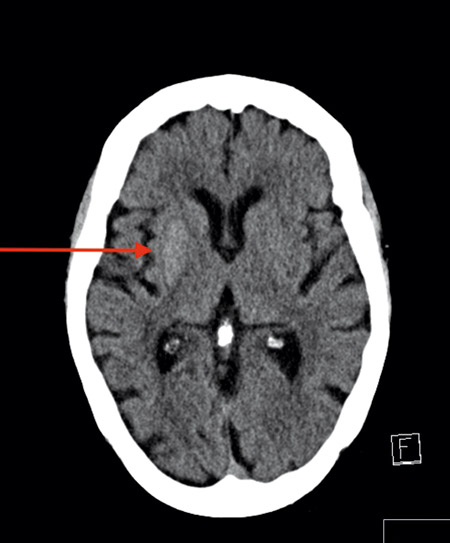

Patienten lades in på intensivvårdsavdelningen under 2 dygn med diagnosen hyperosmolärt non-ketotiskt syndrom för tät monitorering under korrigering av vätskebalans och glukos. Behandlingen bestod initialt av en kombination av Ringer-acetat, Plasmalyte med natriumtillsats, NaCl med tillsats av sterilt vatten, insulin samt glukos med natriumtillsats. På grund av snabbt sjunkande P-glukos och stigande natrium under dag 2 minskades vätsketillförseln och insulindosen. DT av hjärnan gjordes på grund av ansiktsasymmetri med hängande höger mungipa, vilken visade ökad attenuering i putamen samt caput nucleus caudatus (Figur 1). I övrigt sågs inga tecken på färsk infarkt. HbA1c var 136 mmol/mol.

Figur 1. DT av hjärnan hos patienten i fallbeskrivningen dag 2 efter inläggning för hyperglykemi visar lätt ökad attenuering i basala ganglier på höger sida. Patienten hade ingen kliniskt noterbar dyskinesi vid undersökningstillfället.